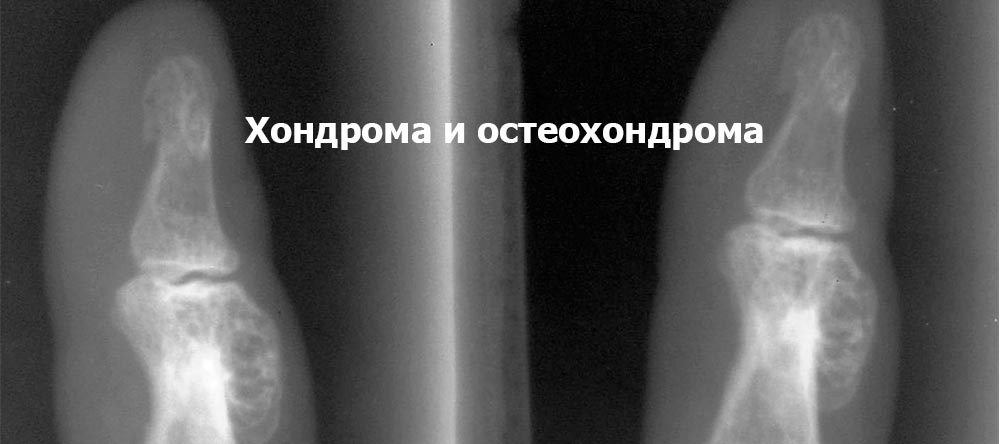

Рентгеновские снимки доброкачественных опухолей костей